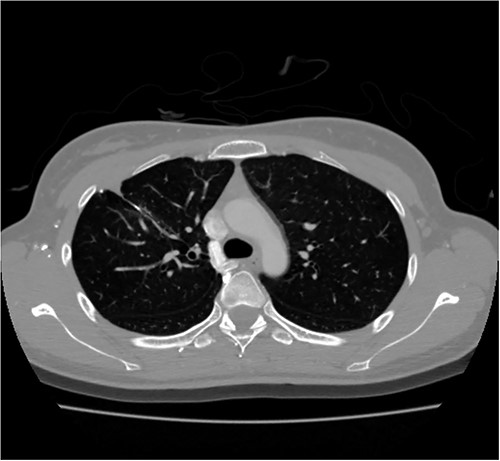

A 24-year-old female in the 21st week of pregnancy was transferred to the emergency department. Twelve hours before admission, the patient developed a tearing pain from the back to the right chest and dyspnea. There was no relevant medical history. Vital signs were systolic blood pressure of 83 mmHg, diastolic blood pressure of 58 mmHg, and pulse rate of 142/min. Initial hemoglobin level was 8.9 g/dl with a platelet count of 99 000/μl. Chest radiographs revealed a massive right pleural effusion with a mediastinal left shift (Fig. 1a). A closed thoracostomy was performed, and 2 l of blood was drained from the pleural cavity. Contrast-enhanced chest computed tomographic scan revealed a potentially ruptured PAVM in the anterior segment of the right upper lung (Fig. 1b). The patient was transfused with five packs of red blood cells and two packs of frozen fresh plasma. Emergency video-assisted thoracoscopic surgery (VATS) was performed. A 5-cm-sized working widow was created in the fifth intercostal space mid-axillary line. Two additional 10.5-mm ports were inserted in the sixth and seventh intercostal spaces in the anterior and posterior axillary lines. A half-liter of blood clots were removed. The PAVM, active bleeding on soft palpation, was visible on the right upper lung surface and was resected with two endostaples (Fig. 2). The patient developed disseminated intravascular coagulation and acute kidney injury postoperatively and was managed in the intensive care unit (ICU) for 3 days. She was recovered and was discharged 6 days after the operation without residual complications. The fetus had no particular problems related to the operation. However, it was miscarried after hydrocephalus and pericardial effusion were discovered. A follow-up computed tomographic scan 8 months after the operation revealed no residual PAVM (Fig. 3).

Radiograph of a 24-year-old woman with chest pain and dyspnea. (a) Chest radiograph showing right massive effusion causing left shifting of the mediastinum. (b) Enhanced axial CT showing the direct connection of a branch of the anterior segmental pulmonary artery (down arrow) with a vein (up arrow) and dilated vessel on the surface of the anterior segment of the right upper lung (arrowhead).

Contrast-enhanced chest CT after 8 months. Chest radiograph reveals no residual PAVM.